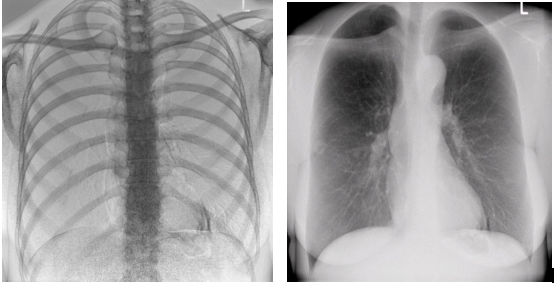

1)大視野無遺漏

17*17英寸的高清像素動態(tài)平板探測器,能對胸部、腹部等部位實現(xiàn)大范圍全覆蓋,動靜態(tài)之間無感切換。透視檢查無須對患者重新定位便可觀察到足夠大的人體器官組織,避免漏診誤診。更好地減少了曝光時間,也減少了病人的輻射劑量。

大尺寸動態(tài)平板技術,覆蓋檢查面積范圍廣,輕松實現(xiàn)胃十二指腸等大面積造影,無需移動即可觀看整個動態(tài)過程,避免噪點對圖像的影響。

2)圖像質(zhì)量無畸變,無失真

高效動態(tài)平板技術,圖像不會有幾何畸變,提供高分辨率和精確的圖像,為臨床診斷提供精準依據(jù)。